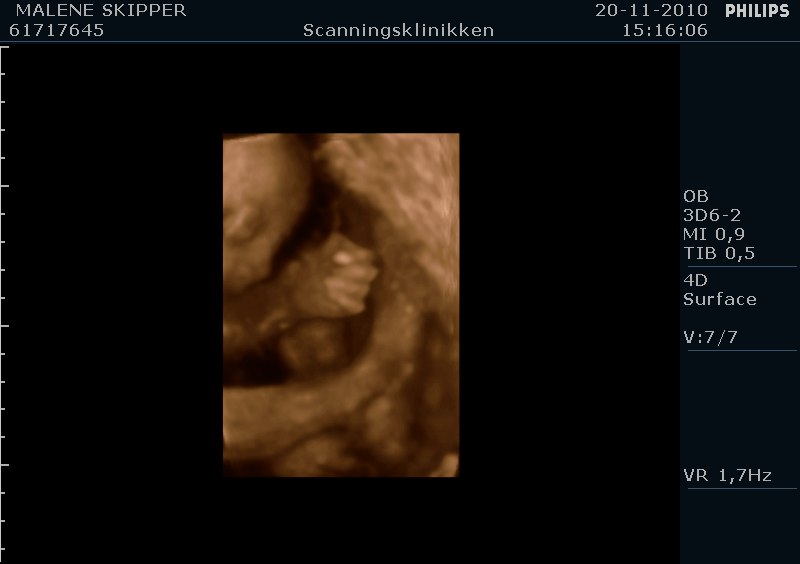

" /> Jeg har været til 4d scanning idag og set vores lille prinsesse som vi er meget stolte af og glæder os til hun kommer ud.. Hun sparker og er livlig hver dag og det er fantastisk..

Her er lige et par billeder fra 4d scanning idag..